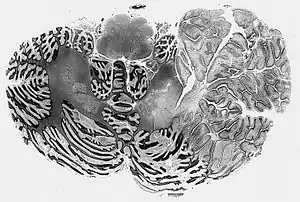

| Dysplastic Cerebellar Ganglioglioma (Lhermitte-Duclos disease) | |